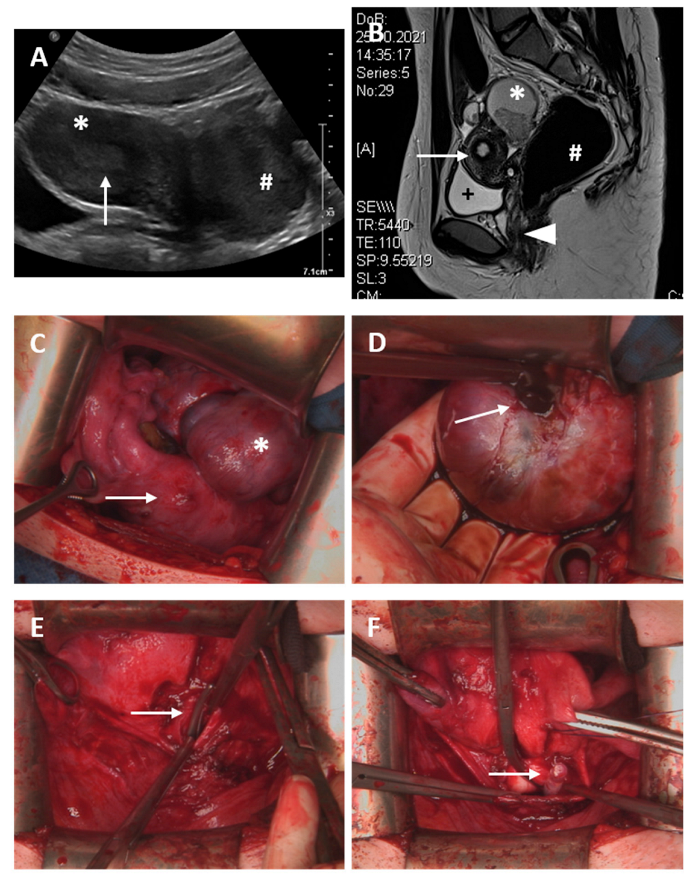

A 17-year-old patient presented with presumed genital malformation. Previously, the patient had undergone surgery for presumed vaginal septum, and a cervix could not be found. The patient had initially presented to her gynecologist at the age of 15 year with primary amenorrhea and moderate cyclic pain. The clinical examination depicted a vaginal length of 5–7 cm with a blind ending. An MRI scan suggested a T-formed uterus, cervical atresia, vaginal septum and enlarged ovaries with cysts on both sides (Figure 4). Diagnostic surgery was performed to identify the exact extent of genital malformation. Laparoscopically, endometriosis could be assured, the uterus presented with a T shape, the cervix uteri seemed to be absent and transverse vaginal septum or partial proximal vaginal aplasia was suspected (ESHRE/ESGE classification: U1a C4 V3/4). In February 2022, uterovaginal anastomosis via Pfannenstiel laparotomy using the push-through technique and resection of the atretic cervical tissue were performed, and a 14 Ch-silicon catheter was inserted into the cervix (Figure 4). Follow-up hysteroscopy and cervical dilation after 5 weeks showed a normal vaginal length with sufficient anastomosis and confirmed the presumed T-shaped uterus with no sign of infection. The next examination for follow-up is scheduled in July 2022.

Figure 4.

Case 6. (A) Transabdominal sonography; * uterus without hematometra; arrow depicts endometrium of 9 mm; # suspected rudimentary horn or myoma. (B) Abdominal magnetic resonance imaging: + full bladder, * suspected ovarian cyst 6 × 4 cm, # dilated rectum; arrow shows suspected T-shaped uterus without hematometra; arrowhead shows vagina; no connection from vagina to uterus. (C) Situs during abdominal laparotomy: arrow marks T-shaped uterus, * left side ovarian cyst of 10 cm diameter, suspicious for endometrioma (D) Incision of the suspected endometrioma and discharge of typical chocolate-like blood (arrow). (E): Insertion of an overhold clamp from the vagina (arrow) establishing a connection between the vagina and uterus. (F): Insertion of a 14 Ch-silicon catheter (arrow). (G) Uterovaginal anastomosis established by circular, non-resorbable Prolene 2.0 sutures (arrow). (H) Hysteroscopy after 5 weeks; sufficient uterovaginal anastomosis; * cavum uteri; arrow shows blue non-resorbable Prolene 2.0 suture.